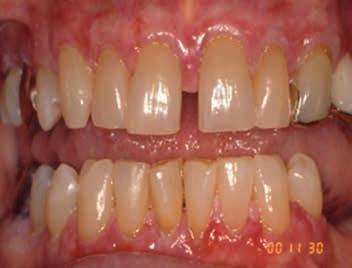

Mucous Membrane Pemphigoid

Figures 3-5. Mucous membrane pemphigoid (MMP) presenting as desquamative gingivitis; poor plaque control resulting from the inability to brush comfortably; patient responded well to topical steroids applied in delivery trays. Figure 3 Figure 4 Figure 5